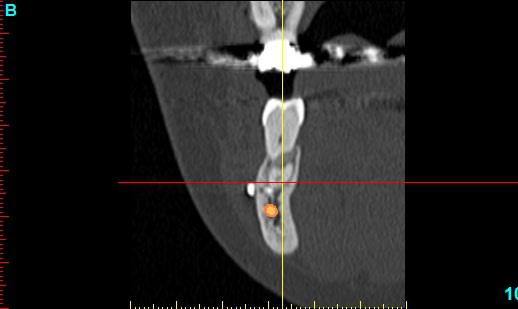

Patiente 58 ans à eu une chirurgie à visée esthétique et "fonctionnelle" adressée pour détartrage en urgence...je ne suis pas spécialiste mais je trouve que la greffe mentonnière est très bof

lésion apicale sur 42 risque de contamination sur la vis en regard..

j'ai demandé un scan en urgence.

Nous sommes d'accord pour la chirurgie mais secteur 4 il y a 2mm être là plastie et la mdble, ça ne me fais pas rêver

Nous sommes d'accord pour la genioplastie je me suis mal exprimé ce qui m'inquiète c'est la proximité de la greffe, pardon genioplastie et de l'infection de 42, d'une part et la mauvaise liaison de la genioplastie secteur 4, mais je suis peut-être pessimiste.

N'ayant aucune donnée j'essaie d'abord de faire le tri,avant de mettre les mains dedans...je raisonne comme en implanto, quand il y a un foyer infectieux à distance proche (42) je pense qu'il y a un risque...

Pour la lésion de 42, ca peut être lié à la genio. Forage hasardeux? Mais je vote plus pour une lésion endo/paro